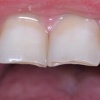

Diasteem – vahe esimeste hammaste vahel. Esineb 50%-l 6-8 aastastel lastel. Kuni 2 mm diasteemi puhul on, peale lateraalse intsisiivi ja silmahamba lõikumist, võimalik diasteemi iseeneslik sulgumine. Diasteem, mille suurus...